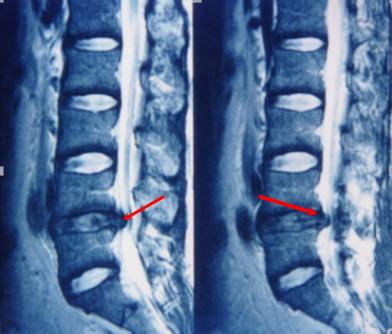

磁共振检查:跟CT一样,具有确诊价值,同时由于其成像原理,对于观察神经以及是否存在神经压迫水肿信号,有独特的优势,也是目前诊断腰椎间盘突出,明确神经压迫的主要检查,老百姓没学过医的也可以看得到的“突出”!